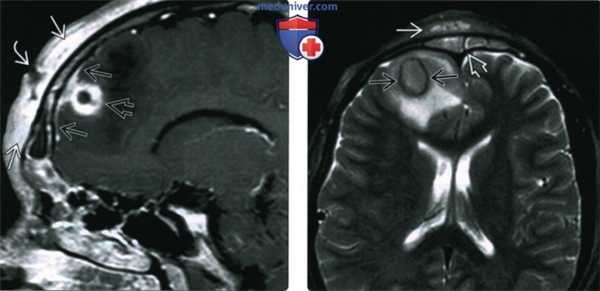

(Слева) При сагиттальной МРТ Т1ВИ С+ определяется утолщение и контрастное усиление мягких тканей лба, соотносящееся с диагнозом «одутловатой» опухоли Попа (подапоневротический абсцесс), обусловленной фронтитом. Обратите внимание на дренирующий синусный тракт. Определяются интракраниальные осложнения: менингит и абсцесс лобной доли.

(Справа) При аксиальной МРТ Т2 ВИ FS определяется отек мягких тканей лба и снижение пневматизации лобных пазух. Визуализируется абсцесс мозга с гипоинтенсивным ободком, окруженный обширным вазогенным отеком.

• Абсцесс мозга:

о Очаг с равномерно утолщенной стенкой и кольцевидным накоплением контраста

о Снижение коэффициента диффузии в центре, ↓ Т1, ↑ Т2

о ↓ Т2 в «кольце», окруженном вазогенным отеком (↑ Т2)